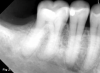

Fig 2. A 63-year-old male patient presented with a chief complaint of spontaneous pain and pressure discomfort of 3-week duration. A distal fracture line was visible on tooth No. 30, with a localized 7 mm deep periodontal probing depth adjacent to its distal aspect. The tooth had no response to pulp sensitivity testing and was sensitive to percussion. Periapical imaging (Fig 2) revealed a tooth with a shallow restoration and early signs of apical pathology. CBCT imaging (Fig 3, axial view, top left; and sagittal view, bottom right) confirmed early signs of apical pathology and showed localized crestal bone loss adjacent to the distal fracture line. A diagnosis of pulpal necrosis with symptomatic apical periodontitis was made, and the fracture was determined to involve root structure given the periodontal findings and radiographic crestal bone loss noted. The patient elected to pursue extraction with implant replacement given the reduced long-term prognosis for maintenance of the tooth.

Figure 2